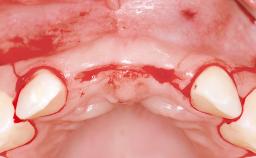

This 20-year-old woman was referred to our department in July 2006. Four months earlier, she had experienced dental trauma to the anterior maxilla when traveling in South America. The emergency treatment included emergency root canal treatment of teeth 12 and 11. Tooth 21 was also subjected to endodontic treatment later. At the initial examination, the patient was not in pain but reported increased mobility of tooth 12. The clinical examination revealed a high smile line, medium thickness of the soft tissue, and rectangular tooth forms. Discoloration of tooth 12 was evident. The periapical radiograph provided by the referring dentist indicated a fracture line at both teeth 12 and 11. A cone-beam computed tomography (CBCT) scan confirmed these fractures. No pathology was found to be associated with tooth 21.

Soft Tissue Anatomy Intact Defective

Bone Volume Horizontally and vertically sufficient Horizontally deficient Deficient vertically or deficient vertically AND horizontally

Bone Volume Deficient horizontally, allowing simultaneous augumentation